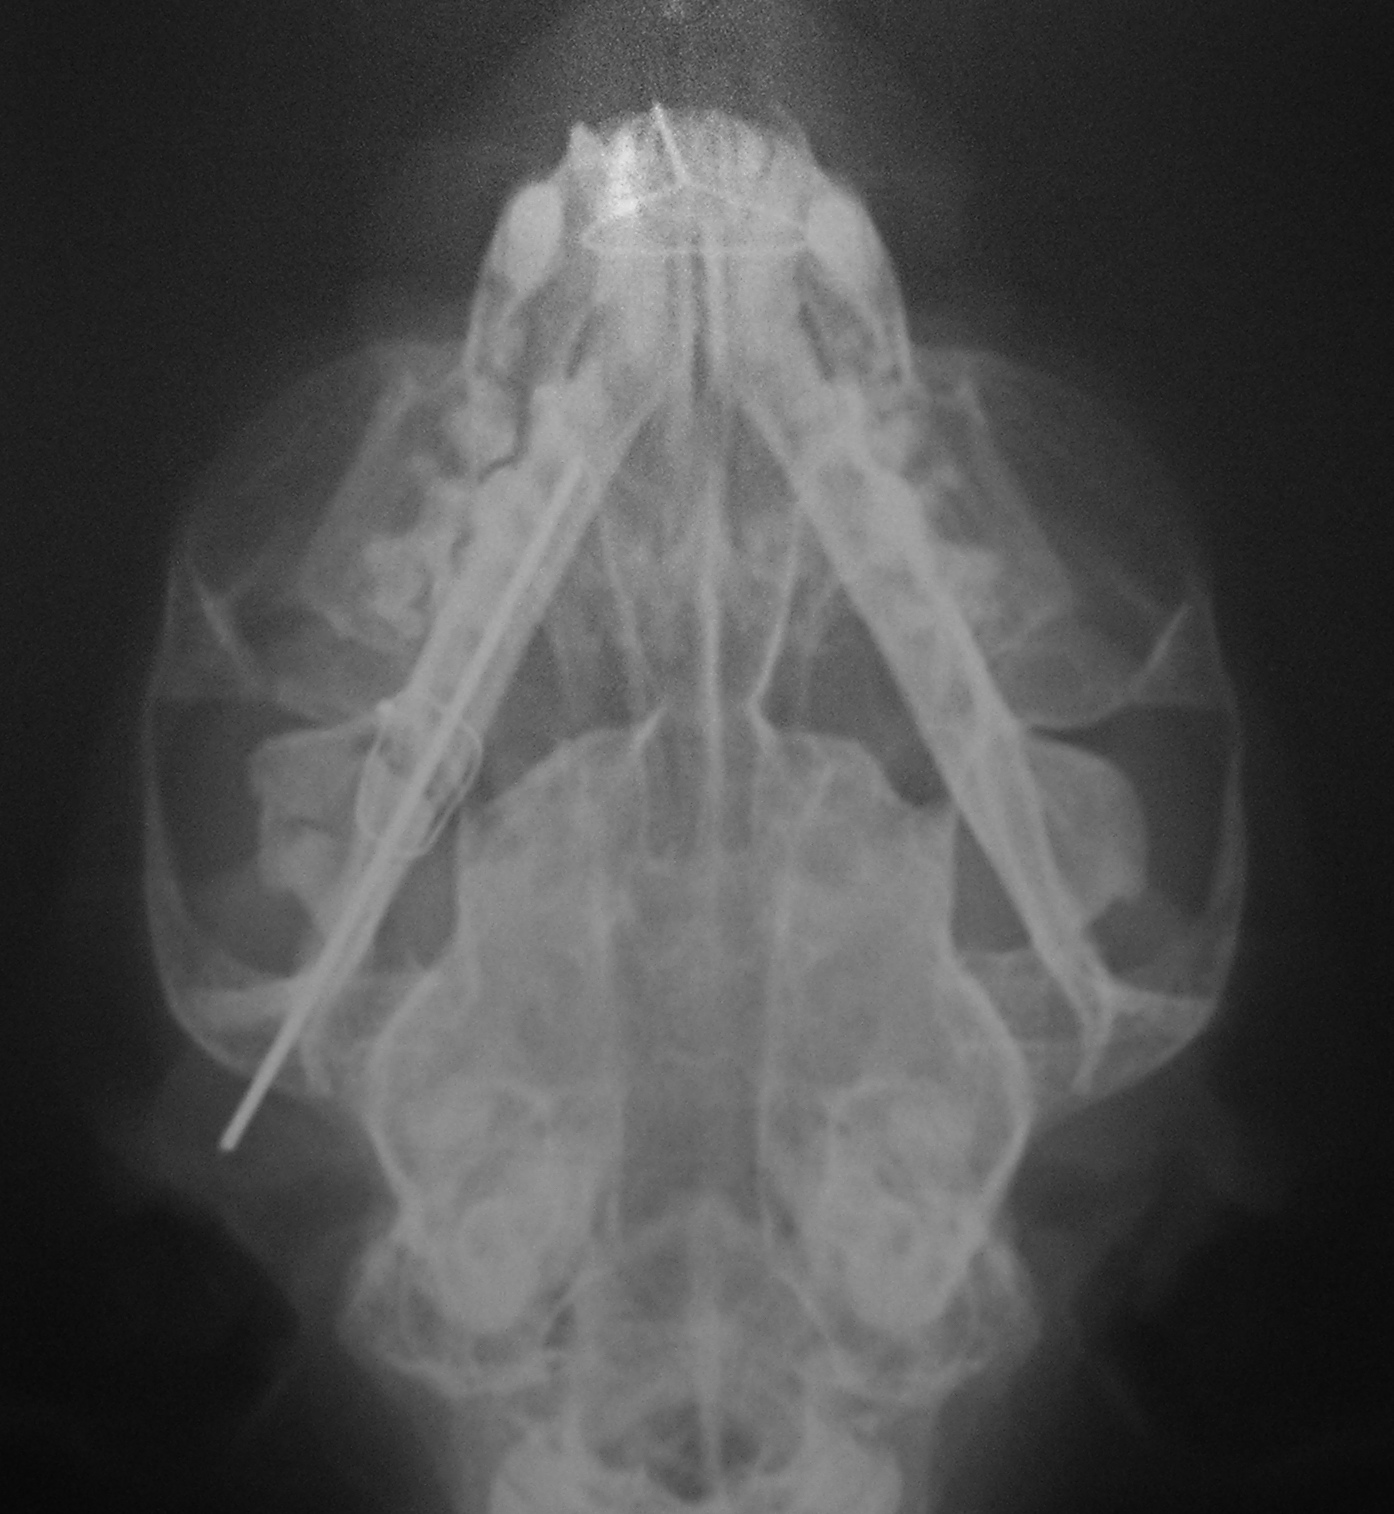

Κατάγματα κάτω γνάθου σε γάτα από Πέτρος Μπεάκος25/11/201007/12/2017Σχολιάστε Παραμόρφωση της κάτω γνάθου λόγω των καταγμάτων Λοξή ακτινογραφία κάτω γνάθου στην οποία φαίνονται τα κατάγματα της γενειακής σύμφυσης και του οπισθίου άκρου της γόμφιας μοίρας του σώματος Μετεγχειρητική ακτινογραφία Η σύγλειση των οδόντων μετεγχειρητικώς Κοινοποιήστε: Στείλε ένα σύνδεσμο σε έναν φίλο(Ανοίγει σε νέο παράθυρο) Email Εκτύπωση(Ανοίγει σε νέο παράθυρο) Εκτύπωση Mοιραστείτε στο Facebook(Ανοίγει σε νέο παράθυρο) Facebook Μοιραστείτε στο X(Ανοίγει σε νέο παράθυρο) Χ Μου αρέσει! Φόρτωση... Σχετικά